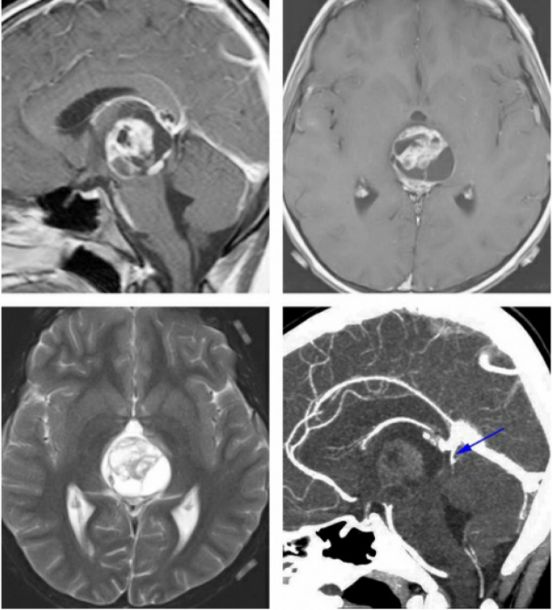

图4. 对于有些患者,术前仔细评估深部静脉系统是有好处的。如图所示为一例未成熟畸胎瘤患者,术前CT血管成像提示大脑大静脉及其属支位于肿瘤后方(蓝色箭头)。这种静脉结构使得我们不能采用显露更好的小脑上入路,而枕部经天幕入路更为合适。

图19. 这是一例顶盖区的低级别星形细胞瘤(上图),术前影像提示大脑大静脉在肿瘤后方(上图,右,蓝色箭头所指)。尽管笔者术中在处理肿瘤时保持对寻找该静脉的高度警惕,但仍然差点损伤它,因为它嵌入了肿瘤中。术后影像(下图)提示肿瘤次全切,这点如术前计划的一样,肿瘤在丘脑内的部分残留。该病例也再次强调了仔细分析术前影像的重要性。